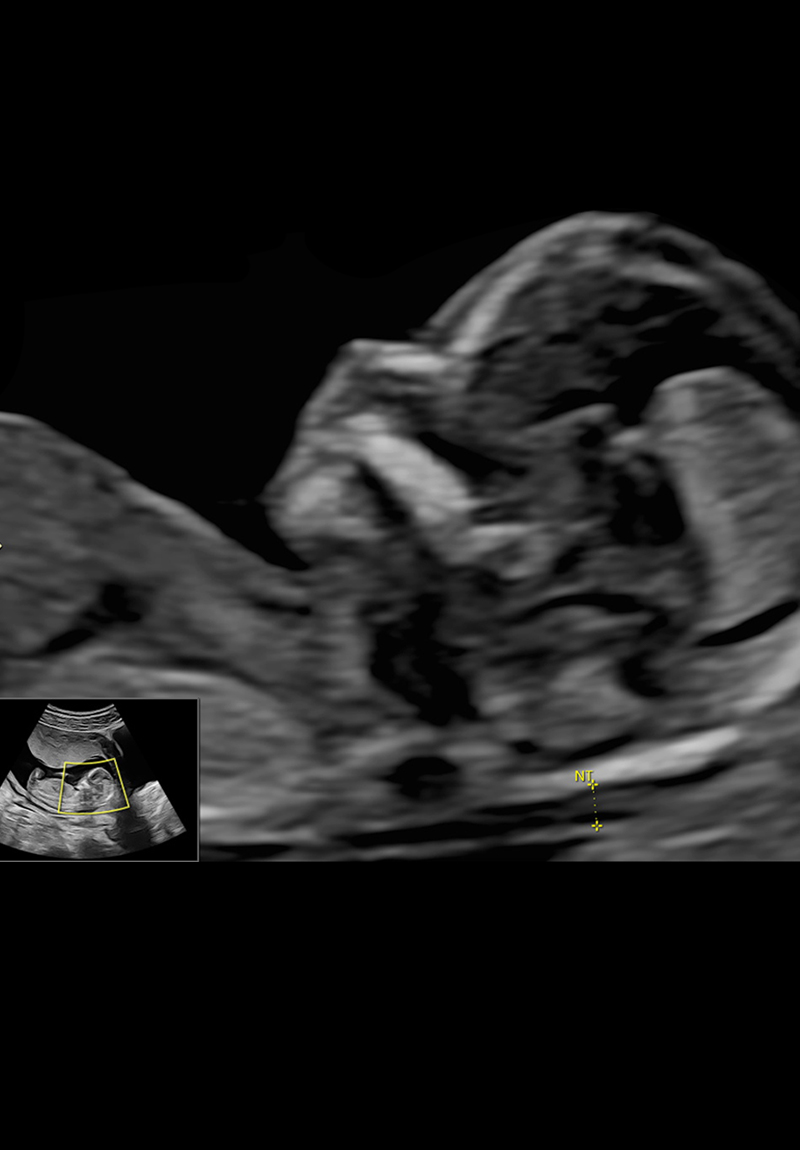

Ecografía Genética: Eco del Primer Trimestre

La ecografía genética, también llamada eco genético o ultrasonido genético, el cual se realiza entre las semanas 11 y 14, es fundamental para el diagnóstico precoz de enfermedades genéticas, como el Síndrome de Down. Además de ofrecer una ventana temprana acerca de la salud genética de bebé, con esta ecografía podemos estimar el riesgo de presentar preeclampsia en el embarazo. Esta última condición puede ser prevenible y evitar que complique la salud de mamá y bebé.